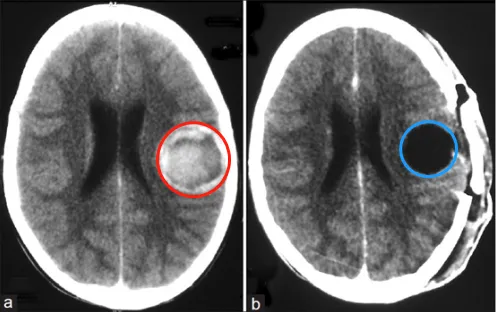

影像学检查显示:矢状位CISS序列可见导水管入口明显狭窄,IRTSE序列显示导水管内脑脊液流动正常,术前T2加权像显示侧脑室宽度正...